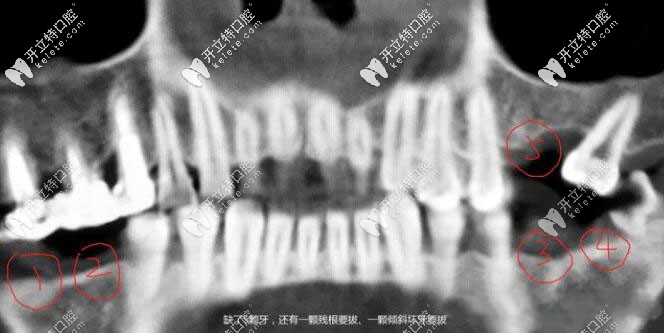

“即刻種植”的種植牙技術(shù),采用的是全數(shù)字化口腔CT掃描,在種植前就能全面獲得牙槽骨的密度、高度、寬度等準(zhǔn)確數(shù)據(jù);

然后再通過計(jì)算模擬口腔的生物力學(xué)、牙槽骨承重力量以及與牙神經(jīng)的距離,精準(zhǔn)計(jì)算后選擇種植體的點(diǎn)位力學(xué)和組織結(jié)構(gòu),避開牙神經(jīng)的密集區(qū),植入人工種植體,并且讓種植體在整個(gè)口腔組織的多角度分力, 也就實(shí)現(xiàn)了“當(dāng)天種牙、當(dāng)天戴牙、當(dāng)天用牙”的效果。